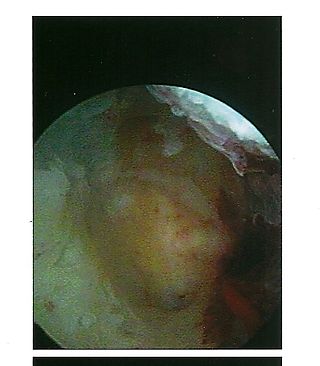

[Tamarika’s womb, taken June 2008]

We struggled together this past year, and yesterday we were finally given a reprieve. As I look, long and hard, at the photograph the doctor took of the inside of my womb last Friday, I see a soft, round, warm, vital, alive, moon-like organ. She looks a little scarred and uneven. Perhaps it is the harsh light shining on her, for she is used to being cradled in darkness. She looks quite miraculous to me. I wish I had known more about her when I was young. I might have taken more care with her. Appreciated her more – appreciated me more.